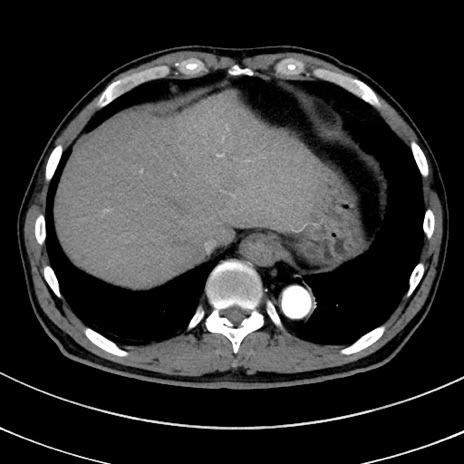

症例8(横断像)

【症例】 60歳代男性

【主訴】 黒色吐物

【現病歴】 4日前から嘔気自覚、2日前の朝食後にも嘔気あり、自分で手で嘔吐反射起こし嘔吐したところ血が混ざっていたため受診。

【既往歴】 5年前汎発性腹膜炎を伴う急性虫垂炎で手術、高血圧、前立腺肥大症、高脂血症

【身体所見】 腹部正中に手術癩痕あり 腹部平坦・軟圧痛なし膨満感あり

【データ】WBC 8400、CRP 4.54